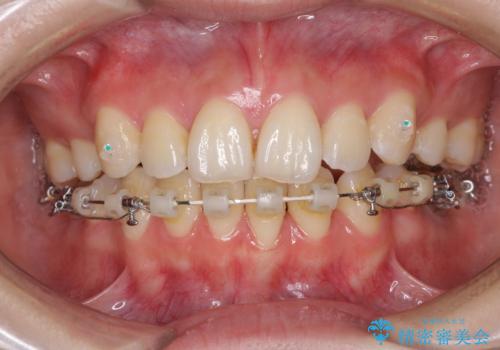

目立たない裏側矯正で突出感を改善 ハーフリンガル矯正

- ハーフリンガル

- 口元の突出感を気にして来院された患者様です。

上下左右の第一小臼歯4本を抜歯して口元を下げる治療計画としました。

裏側矯正特有の抜歯スペースに前後の歯が倒れ込む状態が長く続き、改善に長期間を要しました。